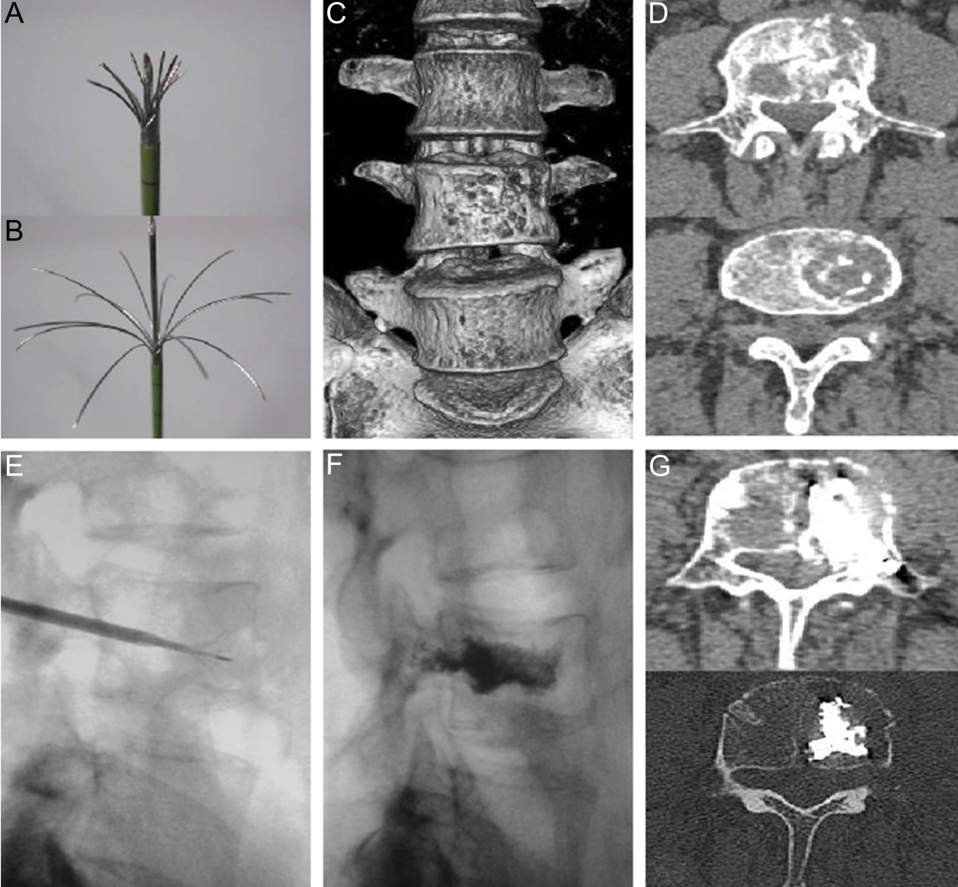

Tiến hành đốt sóng các tổn thương tiêu xương bằng kim chùm.

A. Bệnh nhân nam, 63 tuổi, di căn xương cùng trái từ ung thư biểu mô tế bào vảy (không rõ nguồn gốc).

B. Bệnh nhân nữ 51 tuổi, di căn xương bả vai phải từ ung thư phổi không phải tế bào nhỏ.

Di căn xương từ ung thư trực tràng: A.B. Sử dụng kim đốt sóng cao tần (kim chùm – 13 đầu kim (hooks), tiếp cận thân đốt sống qua cuống sống và tiến hành đốt sóng cao tần khối u di căn, đồng thời bơm xi măng sinh học sau đốt nhiệt